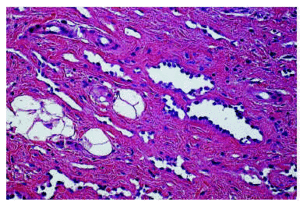

El caso 1 se trata de una mujer de 82 años con induración subcutánea mal definida de 5 cm en cara dorsal de mano derecha, indolora, de varios meses de evolución y crecimiento lento. La resonancia magnética nuclear (RMN) mostró una tumoración subcutánea infiltrativa, mal definida, de 5 cm en el dorso de la mano derecha (fig. 1A). Se realizó biopsia excisional que comprendía un fragmento de tejido subcutáneo grisáceo, homogéneo y firme de 4 x 3 x 2 cm y una pequeña elipse de piel. Tras el diagnóstico anatomopatológico se ampliaron los márgenes quirúrgicos, y al año de seguimiento no se ha producido recidiva ni metástasis.

Fig. 1.--Resonancia magnética nuclear que muestra en A el caso 1: tumoración subcutánea infiltrativa, mal definida, de 5 cm en el dorso de mano. Y en B el caso 2: lesión plantar de 1,2 cm situada en hipodermis que contacta con fascia subyacente.

El caso 2 se trata de una mujer de 31 años con una placa indurada de 1,5 cm en la planta del pie, de varios años de evolución, que en el último año ha aumentado algo de tamaño y se ha vuelto dolorosa. La RMN mostró una lesión de 1,2 cm, situada en hipodermis que contactaba con la fascia subyacente (fig. 1B). Se realizó biopsia incisional. La paciente está a la espera del tratamiento definitivo.